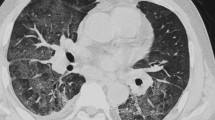

For PCP (Fig. 2), the presence of the mosaic pattern was an indicator (p < 0.001; OR, 9.808; 95% CI, 4.883–19.699) and sensitivity, specificity, PPV, and NPV were 65.7, 88.3, 71.1, and 85.5%, respectively. The absence of nodules was also a significant indicator (p < 0.001; OR, 6.834; 95% CI, 3.438–13.587) and sensitivity, specificity, PPV, and NPV were 79.0, 70.8, 54.2, and 88.5%, respectively (Tables 3 and 4).

Patients with PCP frequently exhibit the mosaic pattern, and nodules with or without cavitation are infrequent [24,25,26]. Nodules and cystic lesions are relatively common in acquired immunodeficiency syndrome (AIDS) patients [24]. The HRCT findings of PCP and CMV-P are often similar, but the differential diagnosis of these is typified by a mosaic pattern and an apical distribution in PCP and an ill-defined demarcation of GGA, consolidation, and nodules with or without a halo sign in CMV-P [27, 28]. These findings of these reports support our results, which identified the presence of a mosaic pattern and the absence of nodules as potential indicators for PCP. We identified the presence of nodules with a halo sign as an indicator for CMV-P, albeit with very low PPV (7.5%).